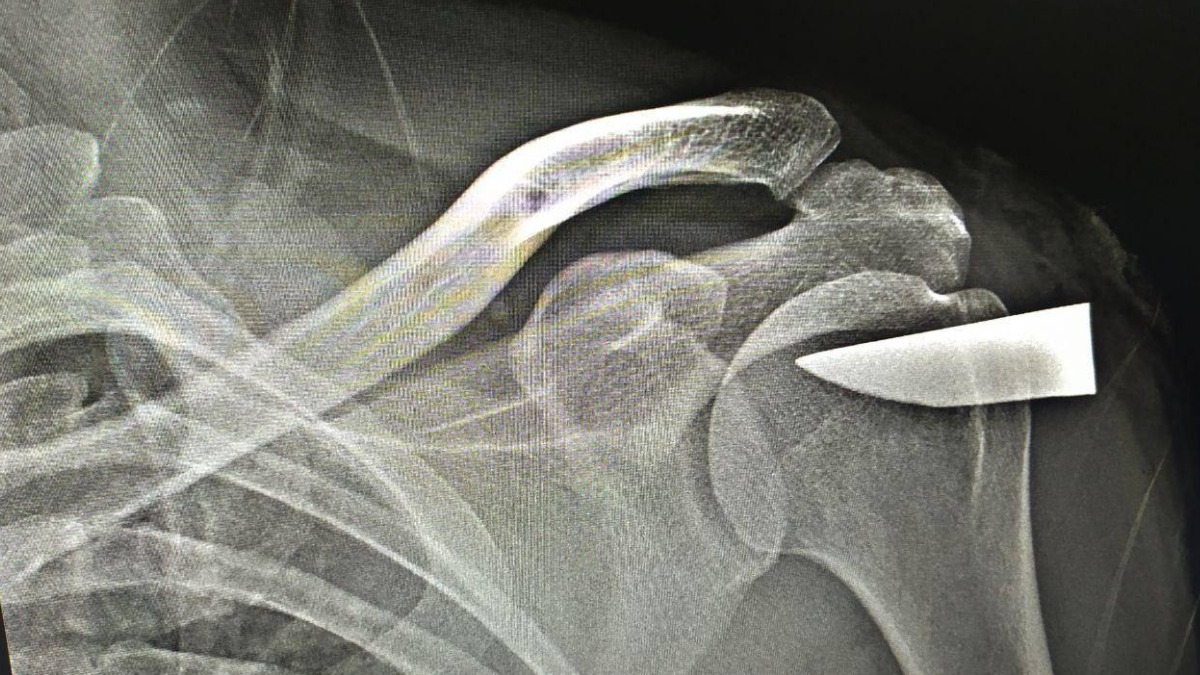

Фото: Пресс-служба Министерства здравоохранения Московской области

Врачи Можайской больницы извлекли из плеча 40-летнего мужчины шестисантиметровый осколок клинка. Об этом в четверг, 26 октября, сообщили в пресс-службе Министерства здравоохранения Московской области.

Мужчина обратился к врачам с жалобами на резаную травму плеча. В ходе рентгена выяснилось, что в суставе застрял кусок клинка. Мужчина не смог вспомнить, при каких обстоятельствах он получил травму.

— По результатам рентген-обследования было установлено, что сталь глубоко вошла в плечевую кость. Специальными кусачками мы извлекли обломок ножа и зашили рану. Пациент, конечно, не ожидал такой «находки» внутри себя. Но обломок оставил себе на память, — рассказал врач — ортопед-травматолог Роман Храмцов.

Операция прошла успешно, пациенту также провели противовоспалительную терапию. В данный момент мужчина чувствует себя хорошо и уже выписан.